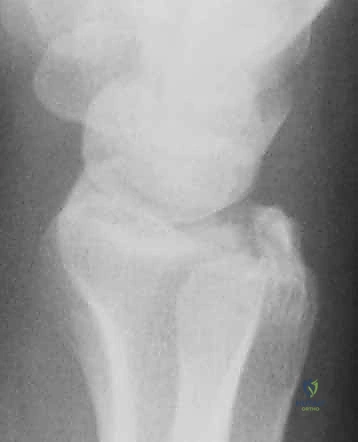

- الكعبرة البعيدة (Distal Radius): هي النهاية السفلية لعظمة الكعبرة (العظمة الأكبر في الساعد من جهة الإبهام). تشكل هذه العظمة الجزء الأكبر والأهم من مفصل الرسغ، وتتحمل حوالي 80% من القوة المنتقلة من اليد إلى الساعد.

- الزند الإبري (Ulnar Styloid): هو النتوء العظمي البارز في النهاية السفلية لعظمة الزند (من جهة الخنصر). يعمل كنقطة ارتكاز هامة للأربطة، وخاصة المعقد الغضروفي الليفي الثلاثي (TFCC)، الذي يعمل كممتص للصدمات ومثبت لمفصل الرسغ.

أي كسر في هذه العظام، خاصة إذا امتد إلى داخل السطح المفصلي (Intra-articular fracture)، سيؤدي إلى اختلال الميكانيكا الحيوية للرسغ بأكمله. إذا لم يتم تسوية السطح المفصلي بدقة متناهية (بحيث لا يتجاوز الفارق 1 مليمتر)، فإن الغضروف سيتآكل بسرعة، مما يؤدي إلى ألم مزمن وخشونة مبكرة.

تحدث هذه الكسور عادة نتيجة لآلية ميكانيكية معروفة طبياً باسم (FOOSH)، وهي السقوط على يد ممدودة (Fall On Outstretched Hand). تختلف شدة الكسر ونوعه بناءً على عدة عوامل منها عمر المريض، قوة العظام، وزاوية السقوط.

- كسر كوليس (Colles' Fracture): كسر في الكعبرة مع انزياح الجزء المكسور إلى الخلف.

- كسر سميث (Smith's Fracture): كسر في الكعبرة مع انزياح الجزء المكسور إلى الأمام.